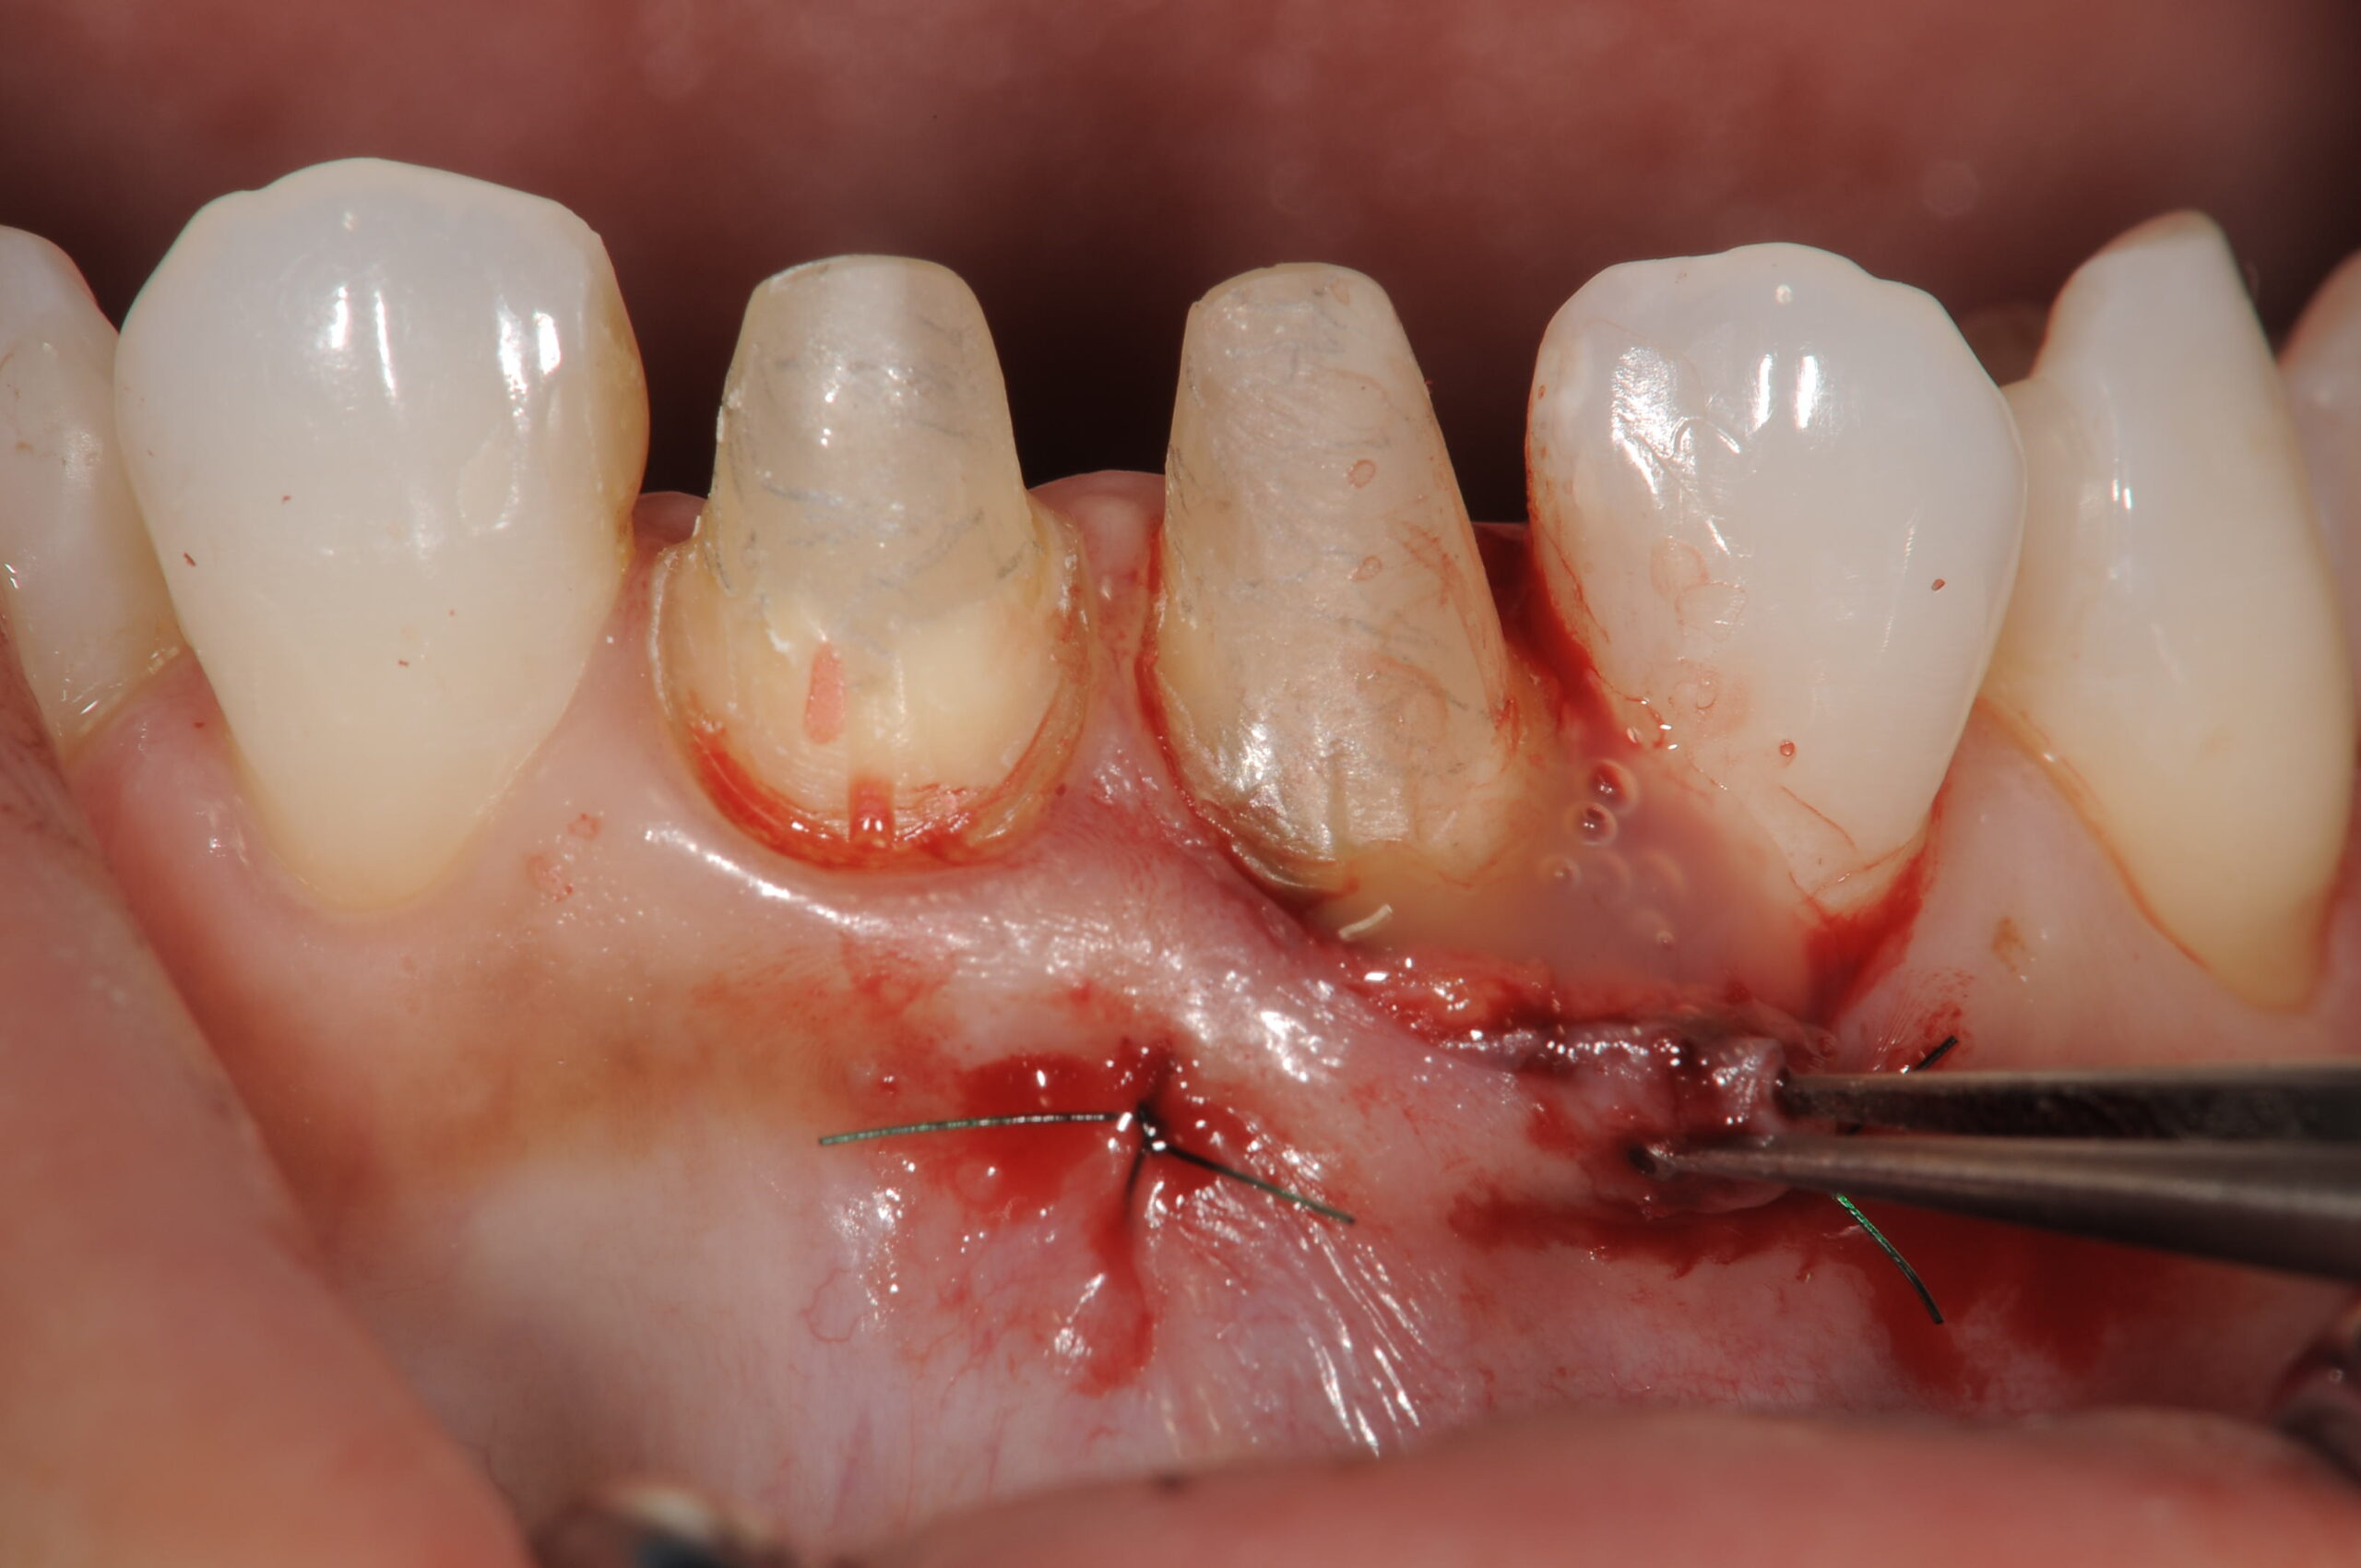

口蓋から採取した結合組織から脂肪組織を除去して綺麗に整形します。

根面上にエムドゲインを塗布する同時に結合組織を移植します。